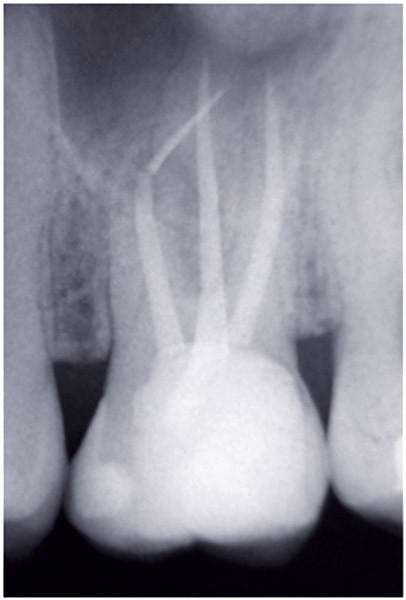

Dans un environnement parodontal sain, la chronologie des traitements conservateurs suite à la pathologie carieuse serait la suivante : le traitement endodontique de première intention, le retraitement endodontique et la chirurgie endodontique, voire l’amputation radiculaire. En cas d’échec, l’alternative implantaire pourra être envisagée (fig. 1).